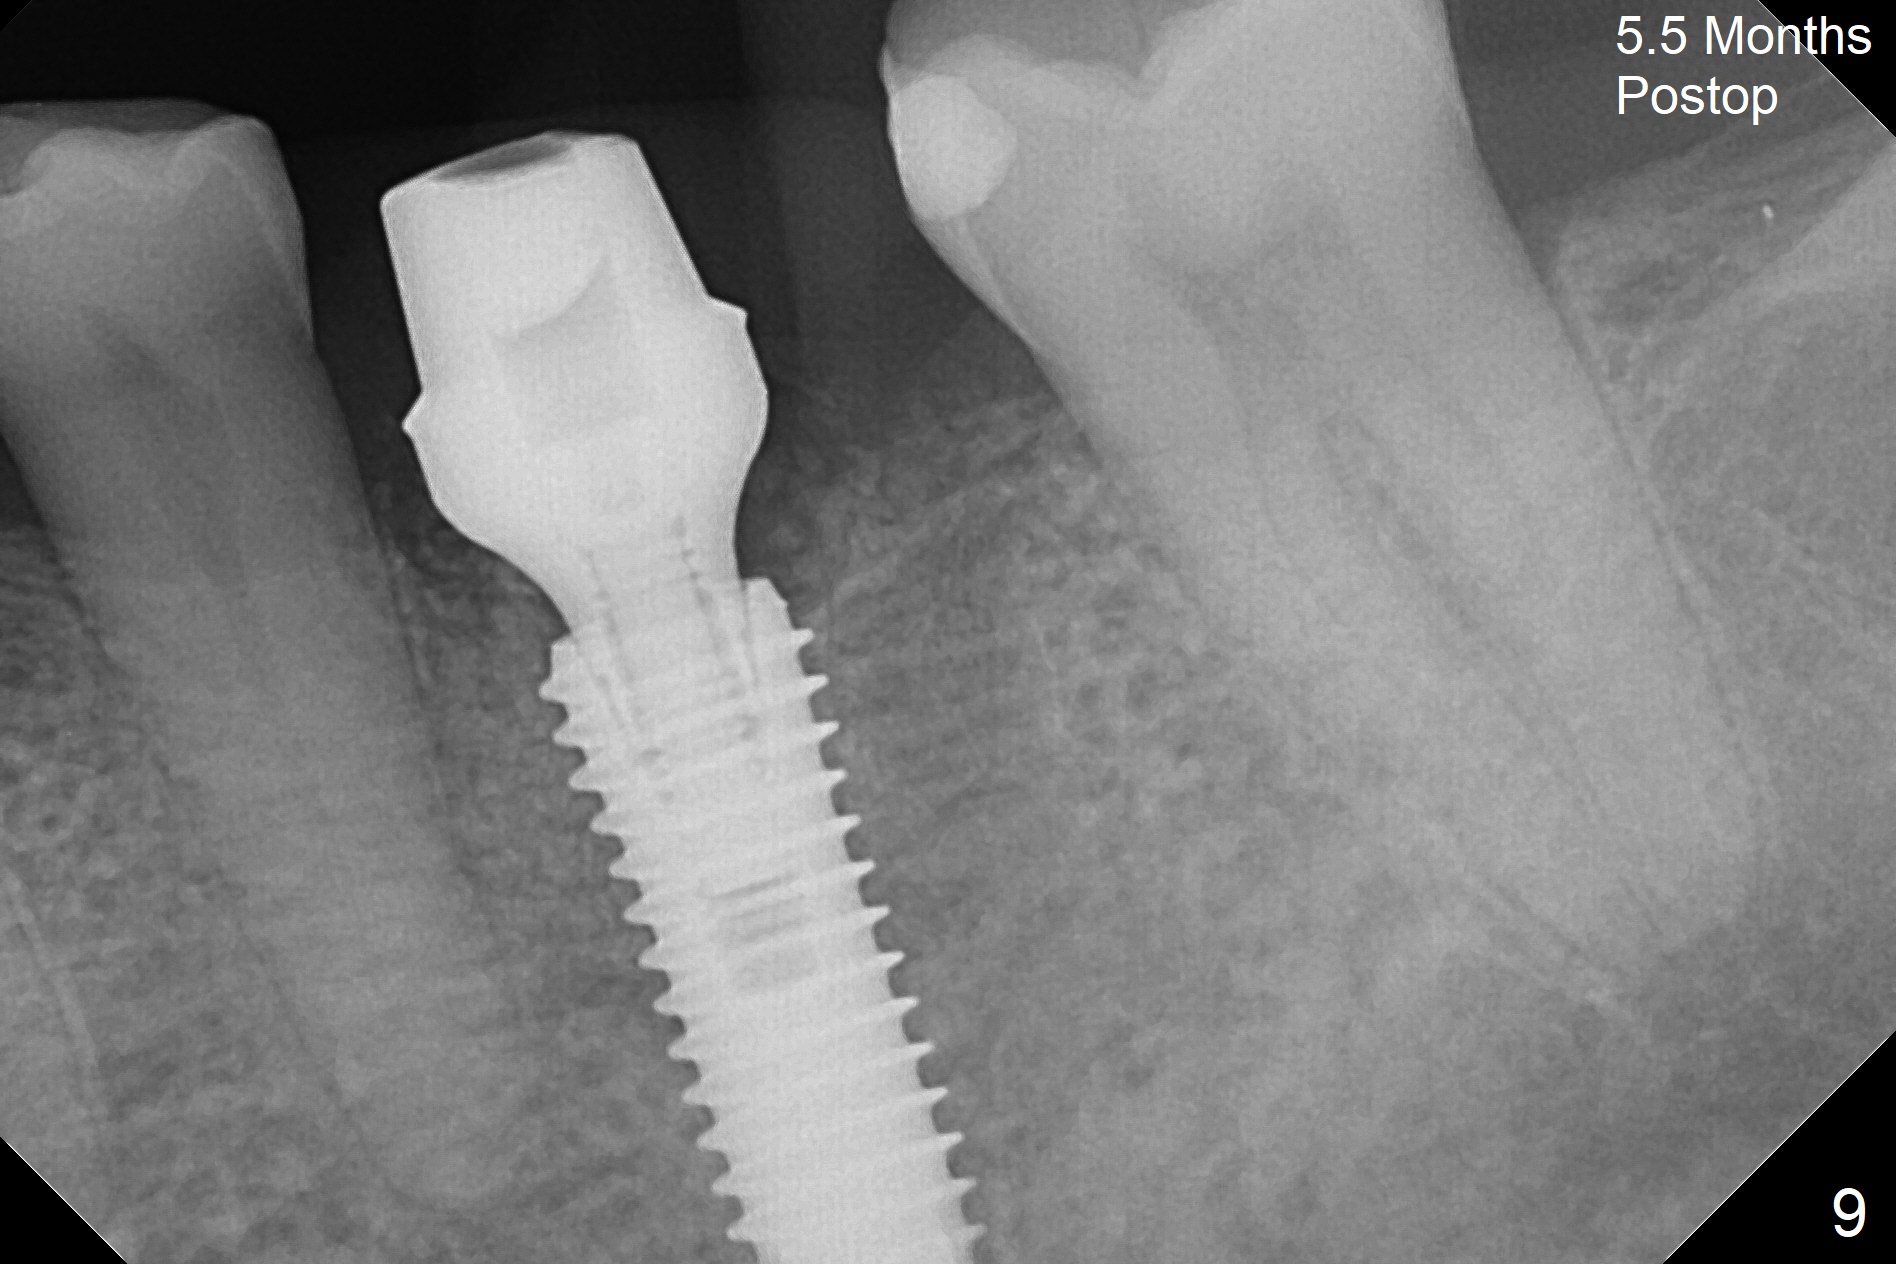

When the patient returns 9 months later, there is severe buccal gingival recession and abscess at #19 (Fig.1 *) with large mesial periradicular radiolucency (Fig.2 *). The septum is thin and the buccal crest is low after extraction (Fig.3 * (mesial root vertical fracture)). Osteotomy is initiated in the mesial socket immediately against the septum (Fig.4.5) with ~ 5 mm in the native bone. Due to severe buccal plate resorption, a shorter implant is placed (Fig.6; 5x15 mm in stead of 18 mm). There is at least 2 mm gap buccally for Vanilla Graft, which is also placed next to the implant and the neighboring root (Fig.7 *). There is clearance from the Inferior Alveolar Canal (Fig.8 red dashed line). Both the mesial and distal sockets heal 5.5 months postop (Fig.9), although the apical portion of the distal socket was not filled with allograft (Fig.7). The implant was placed mesial. The straight abutment (6.5x4(4) mm) (Fig.10) is changed to an angled one (5.5 x15 degrees 3 mm cuff (Fig.11)) before impression. The implant is also placed buccally. Therefore the implant position is far more important than its length. The abutment is retightened 2.5 months post cementation, which is related to mesiobuccal placement of the implant (Fig.12). An ideal trajectory is determined by drawing 2 horizontal lines (at crestal and apical levels: red lines in Fig.13), finding a central point of each line (vertical short line) and joining these 2 central points (Fig.14 pink line). In fact the ideal osteotomy should have been established distal to the septum in this case. Guided surgery may alleviate the issue. The crown is not loose, but the patient feels that the implant tooth cannot sustain mastication. In fact the screw is removed with hand driver (not wrench). The abutment hex is rounded and worn. A new 5.5x4(4) mm abutment is placed (without knowledge of previous use of an angled abutment) with mesial reduction to reduce undercut and buccodistal margin lowered to reduce gingival embrasure. It is that the straight abutment could decrease the chance of screw loosening. Otherwise the implant has to be removed for better trajectory.